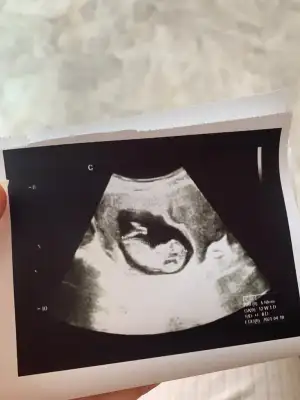

Erkek sanki sankiKızlar ultrason göre nasıl tahmin ediyorsunuz 12 haftalığız biz de

Öncekine de kız gibi emin olamadım dediniz gibi gibi demiştiniz doktor göstermiyor kendini dedi 13. Hafta ya girdikCanım.baska yok mu nubu çok karışıktipi kız gibi öncekine ne demiştim

KizzzKızlar ultrason göre nasıl tahmin ediyorsunuz 12 haftalığız biz de